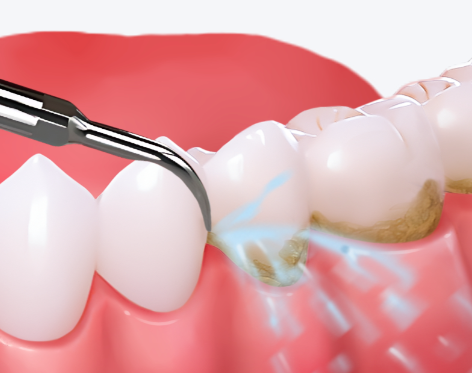

1. 单人超声波喷砂洗牙:100-150元起